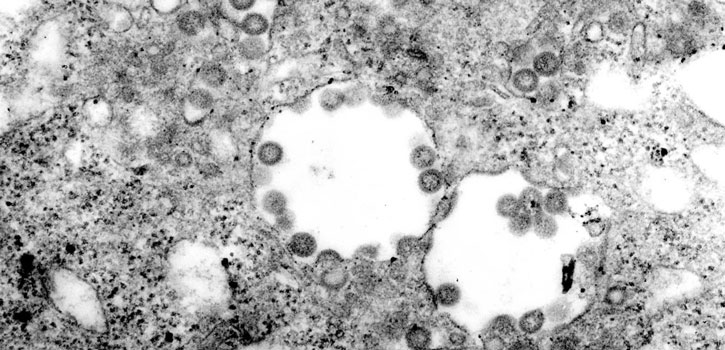

Rift Valley fever virus

Rift Valley fever virus can cause fatal illness in humans, who contract the disease by handling infected animals or animal products. (Photo credit: CDC/F. A. Murphy; J. Dalrymple)

Rift Valley fever virus, transmitted by mosquitoes, causes abortions in cattle, sheep and goats and can kill young animals. The virus also causes severe fever in infected animals and can cause fatal illness in humans, who contract the disease by handling infected animals or animal products.